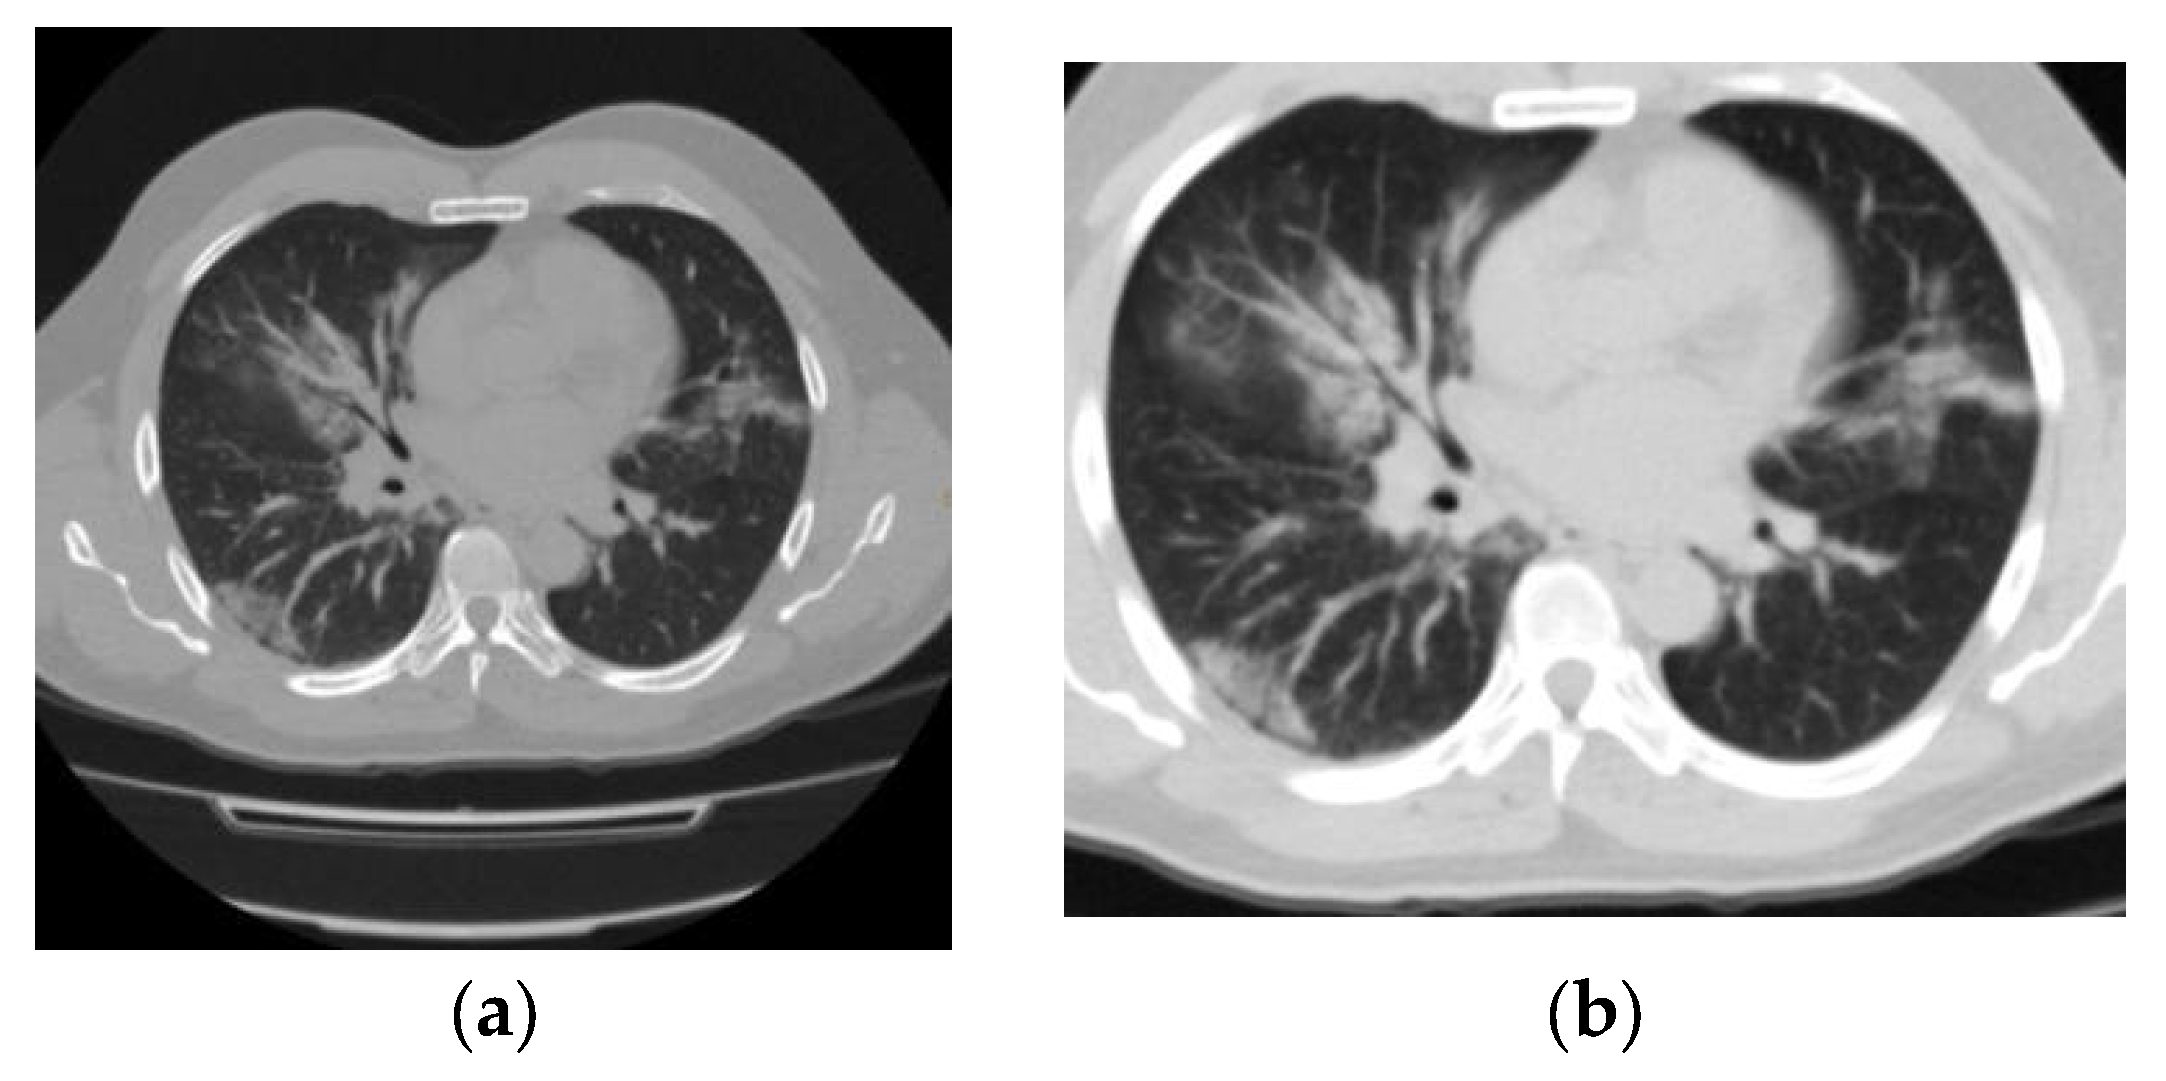

CO-RADS 5: positive; study with typical findings of COVID-19 (Figure 5).

(a) Axial section and (b) axial section (with magnification) show a pattern of multifocal interstitial ground-glass opacity characteristic of pneumonia associated with COVID-19 (SARS-CoV-2) and highly suggestive of the disease in this patient. She was admitted to the intensive care unit after chest CT, showed a positive RT–PCR test result 48 h later, and died 7 days after admission.